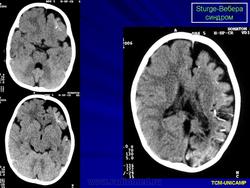

Рентгенологически можно обнаружить обызвествление в затылочных и теменных отделах мозга. При ПЭГ у большинства больных отмечаются атрофия вещества мозга, расширение субарахноидальных щелей на конвекситальной поверхности и расширение полостей желудочков мозга.

Диагноз синдрома Стерджа - Вебера не представляет трудностей. Наличие корковых обызвествлений можно выявить при рентгенографии. Характерные тени располагаются в виде двойных контуров, повторяющих извилины пораженных долей мозга. Компьютерная томография выявляет более обширные области обызвествления, чем это видно при обычной рентгенографии.

Компьютерная томография пациента с болезнью Штурге - Вебера